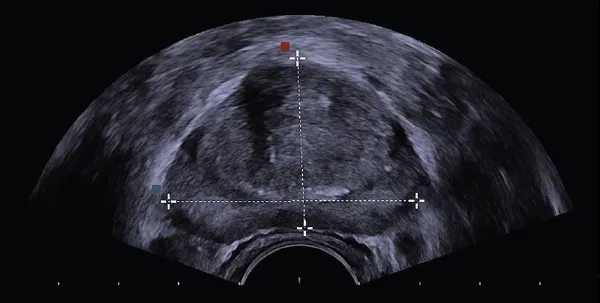

Ocena wielkości i budowy prostaty: Co specjalista widzi na monitorze?

Podczas badania TRUS, na monitorze widzę szczegółowy obraz gruczołu krokowego. Oceniam jego wielkość, kształt i ogólną budowę. Mierzę objętość prostaty, co jest istotne w diagnostyce łagodnego rozrostu stercza (BPH). Zwracam uwagę na echostrukturę, czyli jednorodność tkanki. Szukam wszelkich nieprawidłowości, takich jak torbiele, zwapnienia czy obszary o zmienionej echogeniczności, które mogą sugerować obecność zmian patologicznych.

Zmiany ogniskowe i obszary hipoechogeniczne: Co mogą oznaczać?

Jednym z kluczowych elementów, na które zwracamy uwagę, są zmiany ogniskowe, a w szczególności obszary hipoechogeniczne. Są to miejsca, które na obrazie USG wydają się ciemniejsze niż otaczająca je tkanka. Niestety, obszary hipoechogeniczne mogą sugerować obecność nowotworu prostaty. Ważne jest jednak, aby pamiętać, że nie każda taka zmiana oznacza raka. Mogą one być również wynikiem stanów zapalnych, blizn czy innych łagodnych schorzeń. Dlatego też, w przypadku ich wykrycia, zazwyczaj konieczna jest dalsza diagnostyka, najczęściej w postaci biopsji.